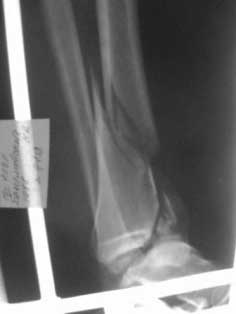

Пилон

Уважаемые коллеги, хотелось бы услышать как прооперировать этот злополучный перелом (интересует погружной синтез)?

Извините за качество снимков! Если сможете разобрать, то: 1)Какой доступ предпочтительней? 2)Каким образом устранить тенденцию к подвывиху кпереди (не будет ли проблемой оскольчатость переднего края)?